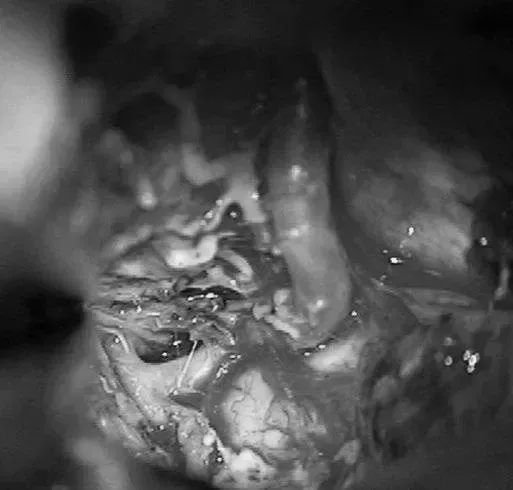

▼右侧眶颧开颅,经侧裂入路,牵开颞极暴露来自ICA鞍上段、MCA的M1段、PCA的P2段和小脑幕切迹。

▼电凝供应颞叶内侧面型AVM的PCA的P2供血支,减少畸形团血供。